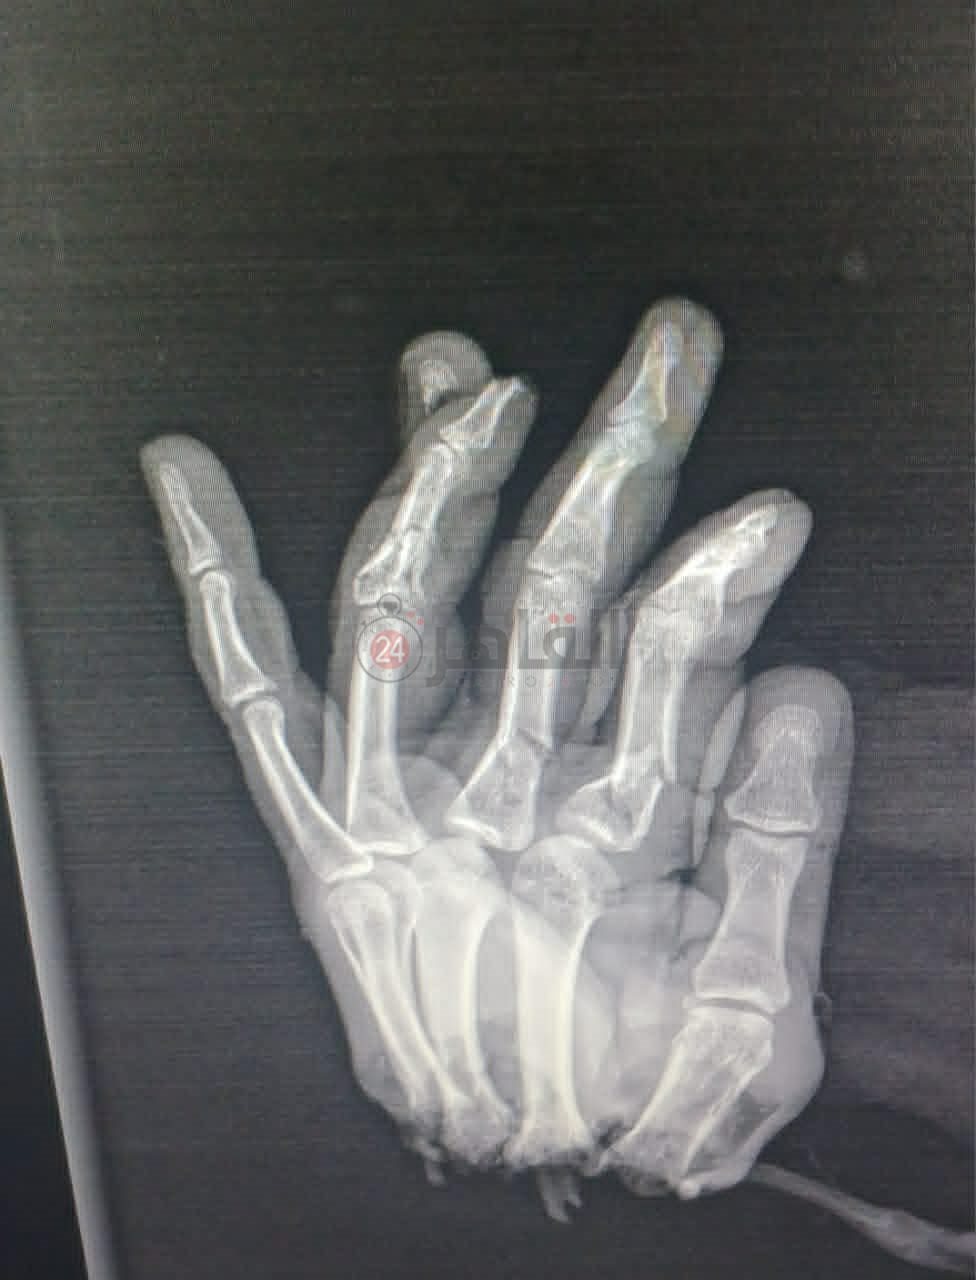

تمكن أطباء قسم جراحة التجميل والحروق بمستشفى سيد جلال الجامعي التابع لجامعة الأزهر من إجراء جراحة لإعادة يد شاب بعد قطعها بالكامل خلال عمله بحقله.

وقال مصدر لـ القاهرة 24، إن أطباء جراحة التجميل والحروق بمستشفى سيد جلال الجامعي بباب الشعرية وبمساعدة أطباء العظام والتخدير بالمستشفى تمكنوا من إعادة توصيل يد مبتورة بالكامل لشاب عامل يبلغ من العمر 37 عامًا، حيث قطعت خلال عمله على ماكينة لجمع أحد المحاصيل بأرضه، وقد استغرقت العملية 16 ساعة متواصلة.